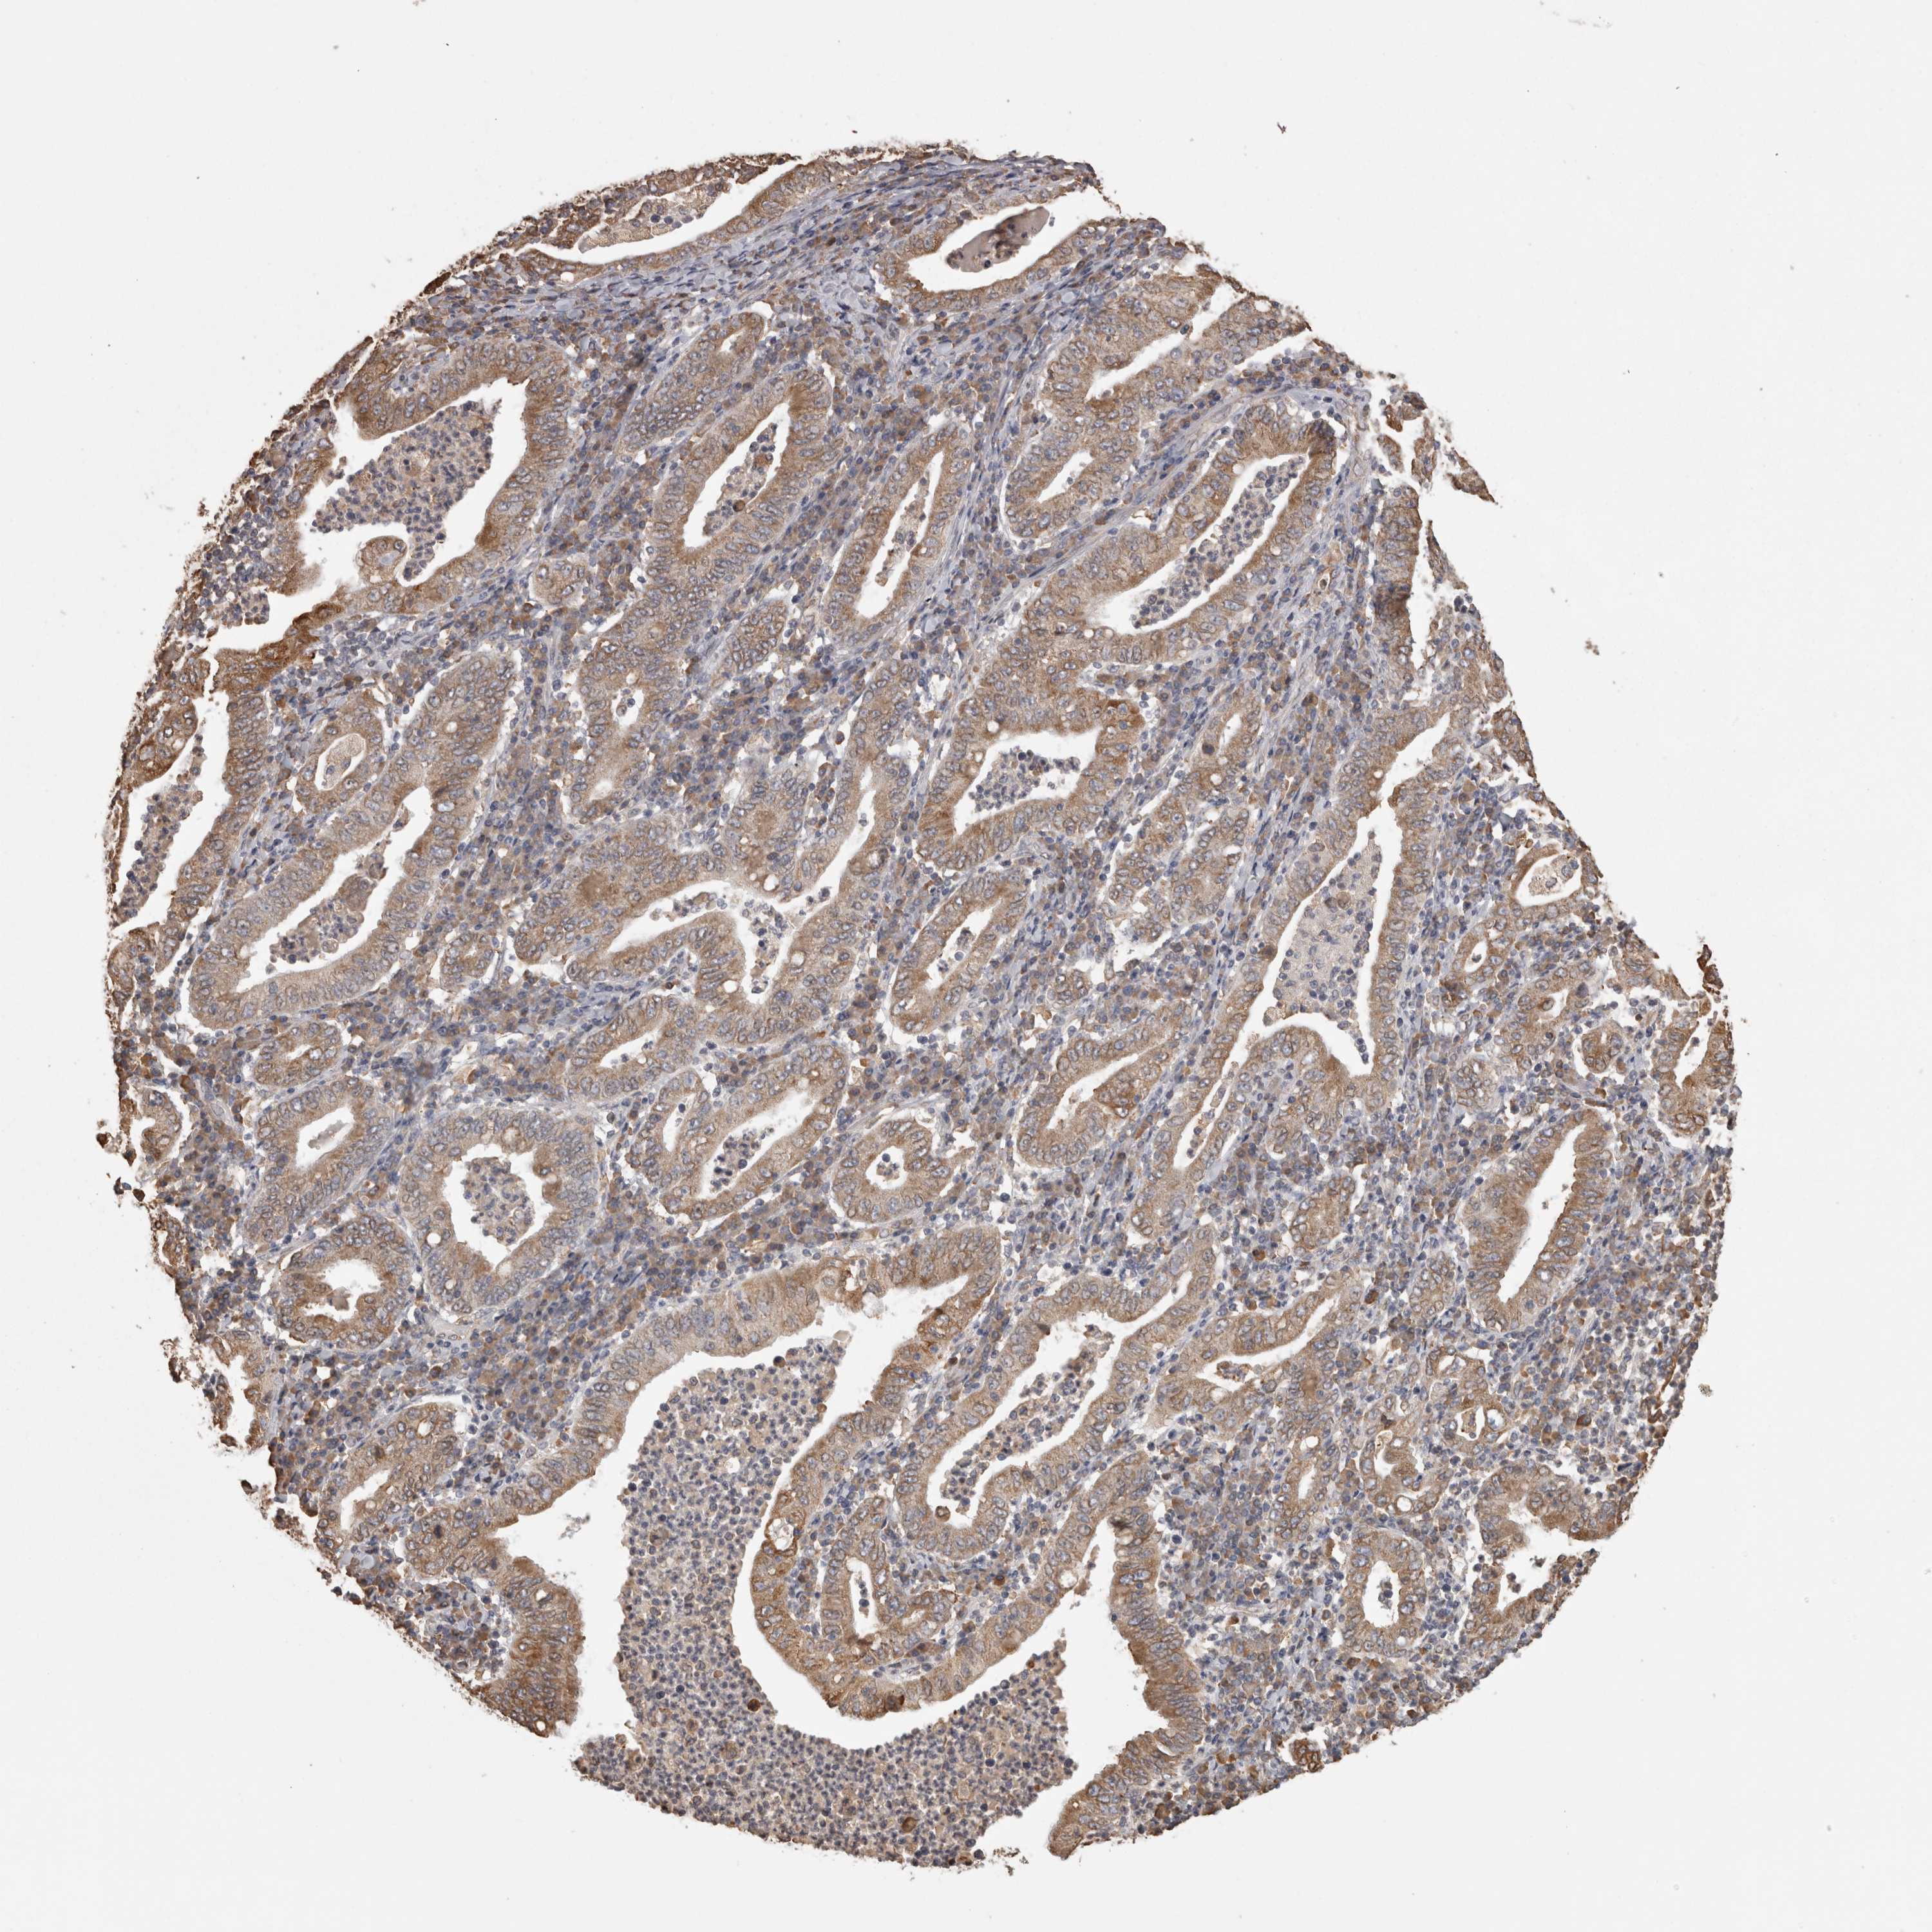

STOMACH CANCER - Protein expressioni

A mouse-over function shows sample information and annotation data. Click on an image to view it in a full screen mode. Samples can be filtered based on level of antibody staining by selecting one or several of the following categories: high, medium, low and not detected. The assay and annotation is described here.

Note that samples used for immunohistochemistry by the Human Protein Atlas do not correspond to samples in the TCGA dataset.

Antibody stainingi

Antibody staining in the annotated cell types in the current human tissue is reported as not detected, low, medium, or high, based on conventional immunohistochemistry profiling in selected tissues. This score is based on the combination of the staining intensity and fraction of stained cells.

Each image is clickable and will lead to virtual microscopy that enables deeper exploration of all samples and also displays staining intensity scores, fraction scores and subcellular localization as well as patient and tissue information for each sample.

Antibody HPA029193

Antibody CAB025430

Staining

High

Medium

Low

Not detected

Intensity

Strong

Moderate

Weak

Negative

Quantity

>75%

75%-25%

<25%

None

Location

Nuclear

Cytoplasmic/membranous

Cytoplasmic/membranous,nuclear

Adenocarcinoma, NOS

Adenocarcinoma, High grade